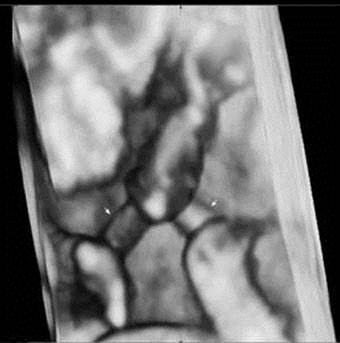

Fig 1

A three-dimensional ultrasound image demonstrates that each fetal umbilical cord (arrow) is entangled at 14weeks of gestation.

Although umbilical cord entanglement has been previously diagnosed with 2D ultrasound, it was difficult to confirm umbilical cord entanglement. Sherer et al. reported that they found umbilical cord entanglement on the transvaginal 2D color Doppler sonogram at 12 weeks' gestation [10]. However, it was difficult for the patient and her family to understand and accept that umbilical cord entanglement had occurred. Although the diagnosis can be made with 2D Doppler, 3D images provide clearer visualization of the cord entanglement and can help illustrate the problem to the parents. The cases using 3D images have been rarely reported and most 3D ultrasounds are conducted in the third trimester of pregnancy [11-13]. Yet, to date, our case is the first to diagnose umbilical cord entanglement by using 3D ultrasound at the first trimester. After delivery, the shape of umbilical cord entanglement was the same as that seen in the 3D ultrasound image. This finding supported a hypothesis that umbilical cord entanglement of monoamniotic twins occurred from the first trimester of pregnancy when the amount of amniotic fluid was relatively large compared to the size of the fetuses and they actively moved [14].